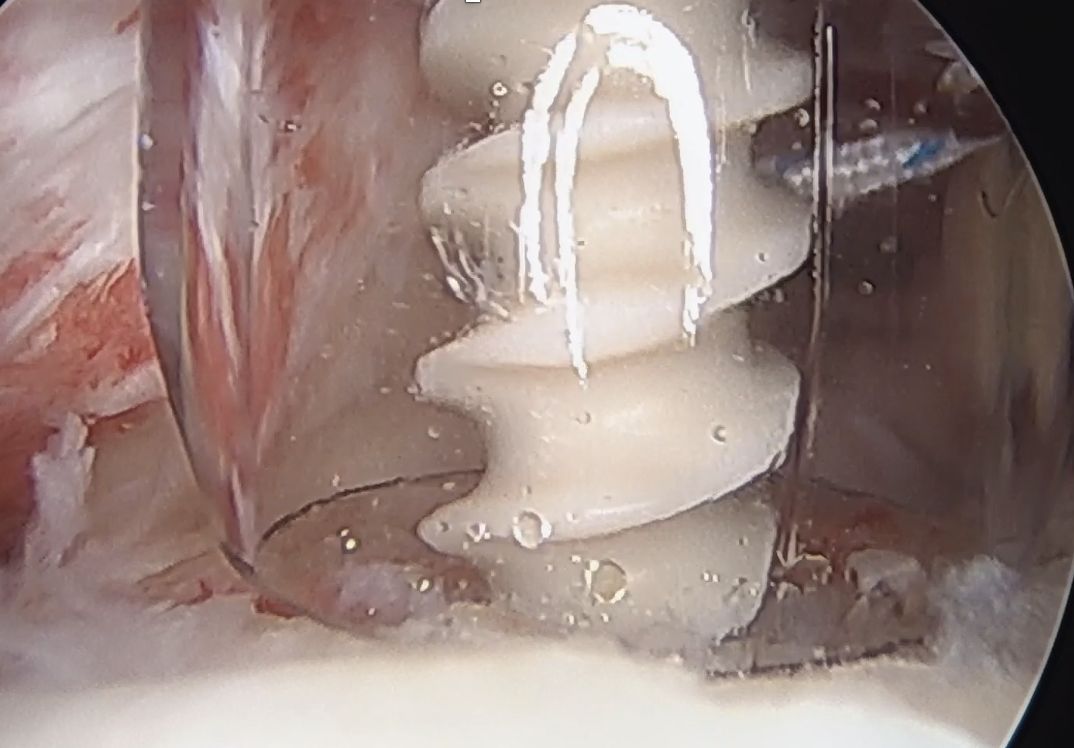

Comma sign

- medially retracted subscapularis tear

- exposes the superior insertion of superior glenohumeral ligament / coracohumeral ligament

Full thickness retracted subscapularis tear with comma sign

Full thickness completely retracted subscapularis, loss of rotator interval and comma sign

Full thickness completely retracted subscapularis, loss of rotator interval and comma sign